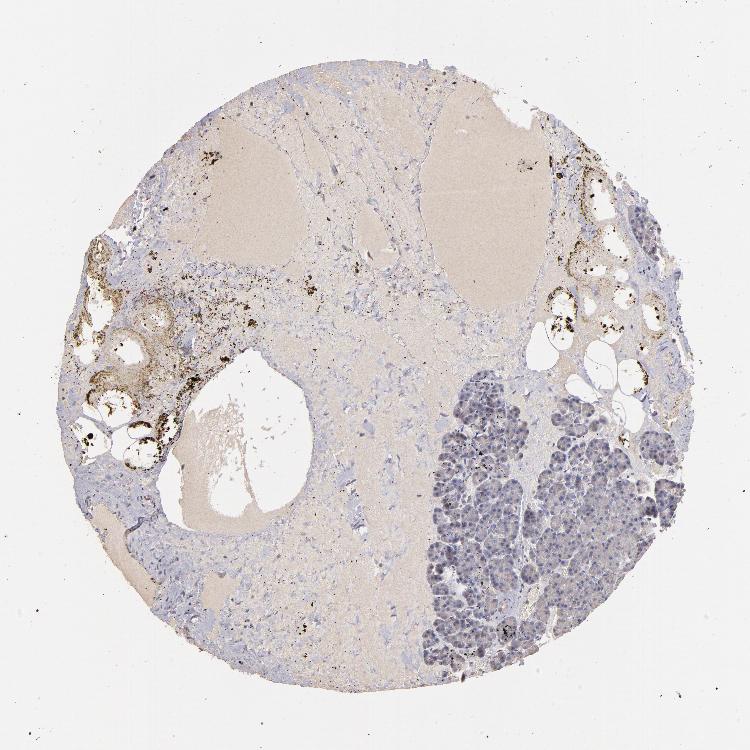

PANCREAS - Antibody stainingi

Antibody staining in the annotated cell types in the current human tissue is reported as not detected, low, medium, or high, based on conventional immunohistochemistry profiling in selected tissues. This score is based on the combination of the staining intensity and fraction of stained cells.

Each image is clickable and will lead to virtual microscopy that enables deeper exploration of all samples and also displays staining intensity scores, fraction scores and subcellular localization as well as patient and tissue information for each sample.

Antibody HPA003011

Exocrine glandular cells Low

Pancreatic endocrine cells High